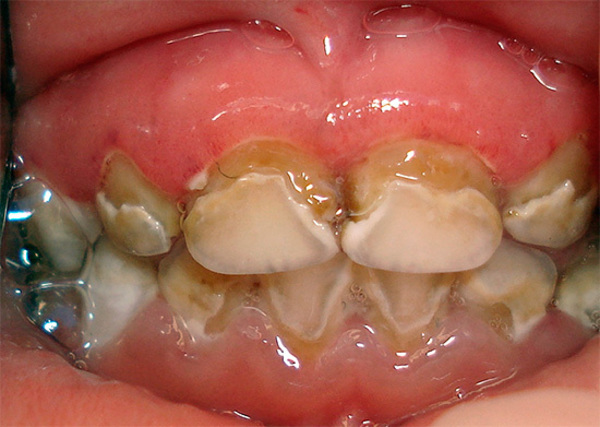

Данная форма включает в себя воспаления, возникающие у детей и подростков. Это может быть препубертатный пародонтит, ювенильный пародонтит или неопределенная болезнь пародонта. Чаще всего заболевание вызвано патогенными бактериями.

Фото 4. Рано возникающий пародонтит. Заболевание наблюдается у ребенка из-за несоблюдения гигиены полости рта.

Препубертатный

Такая форма пародонтита возникает, когда прорезываются постоянные зубы. Встречается достаточно редко и может быть как локализованная, так и генерализованная. Характеризуется ранним выпадением молочных зубов из-за нарушения прикрепления десны. Десневая ткань при этом воспаляется, появляется небольшой отек. Возможно появление кровоточащих трещин.